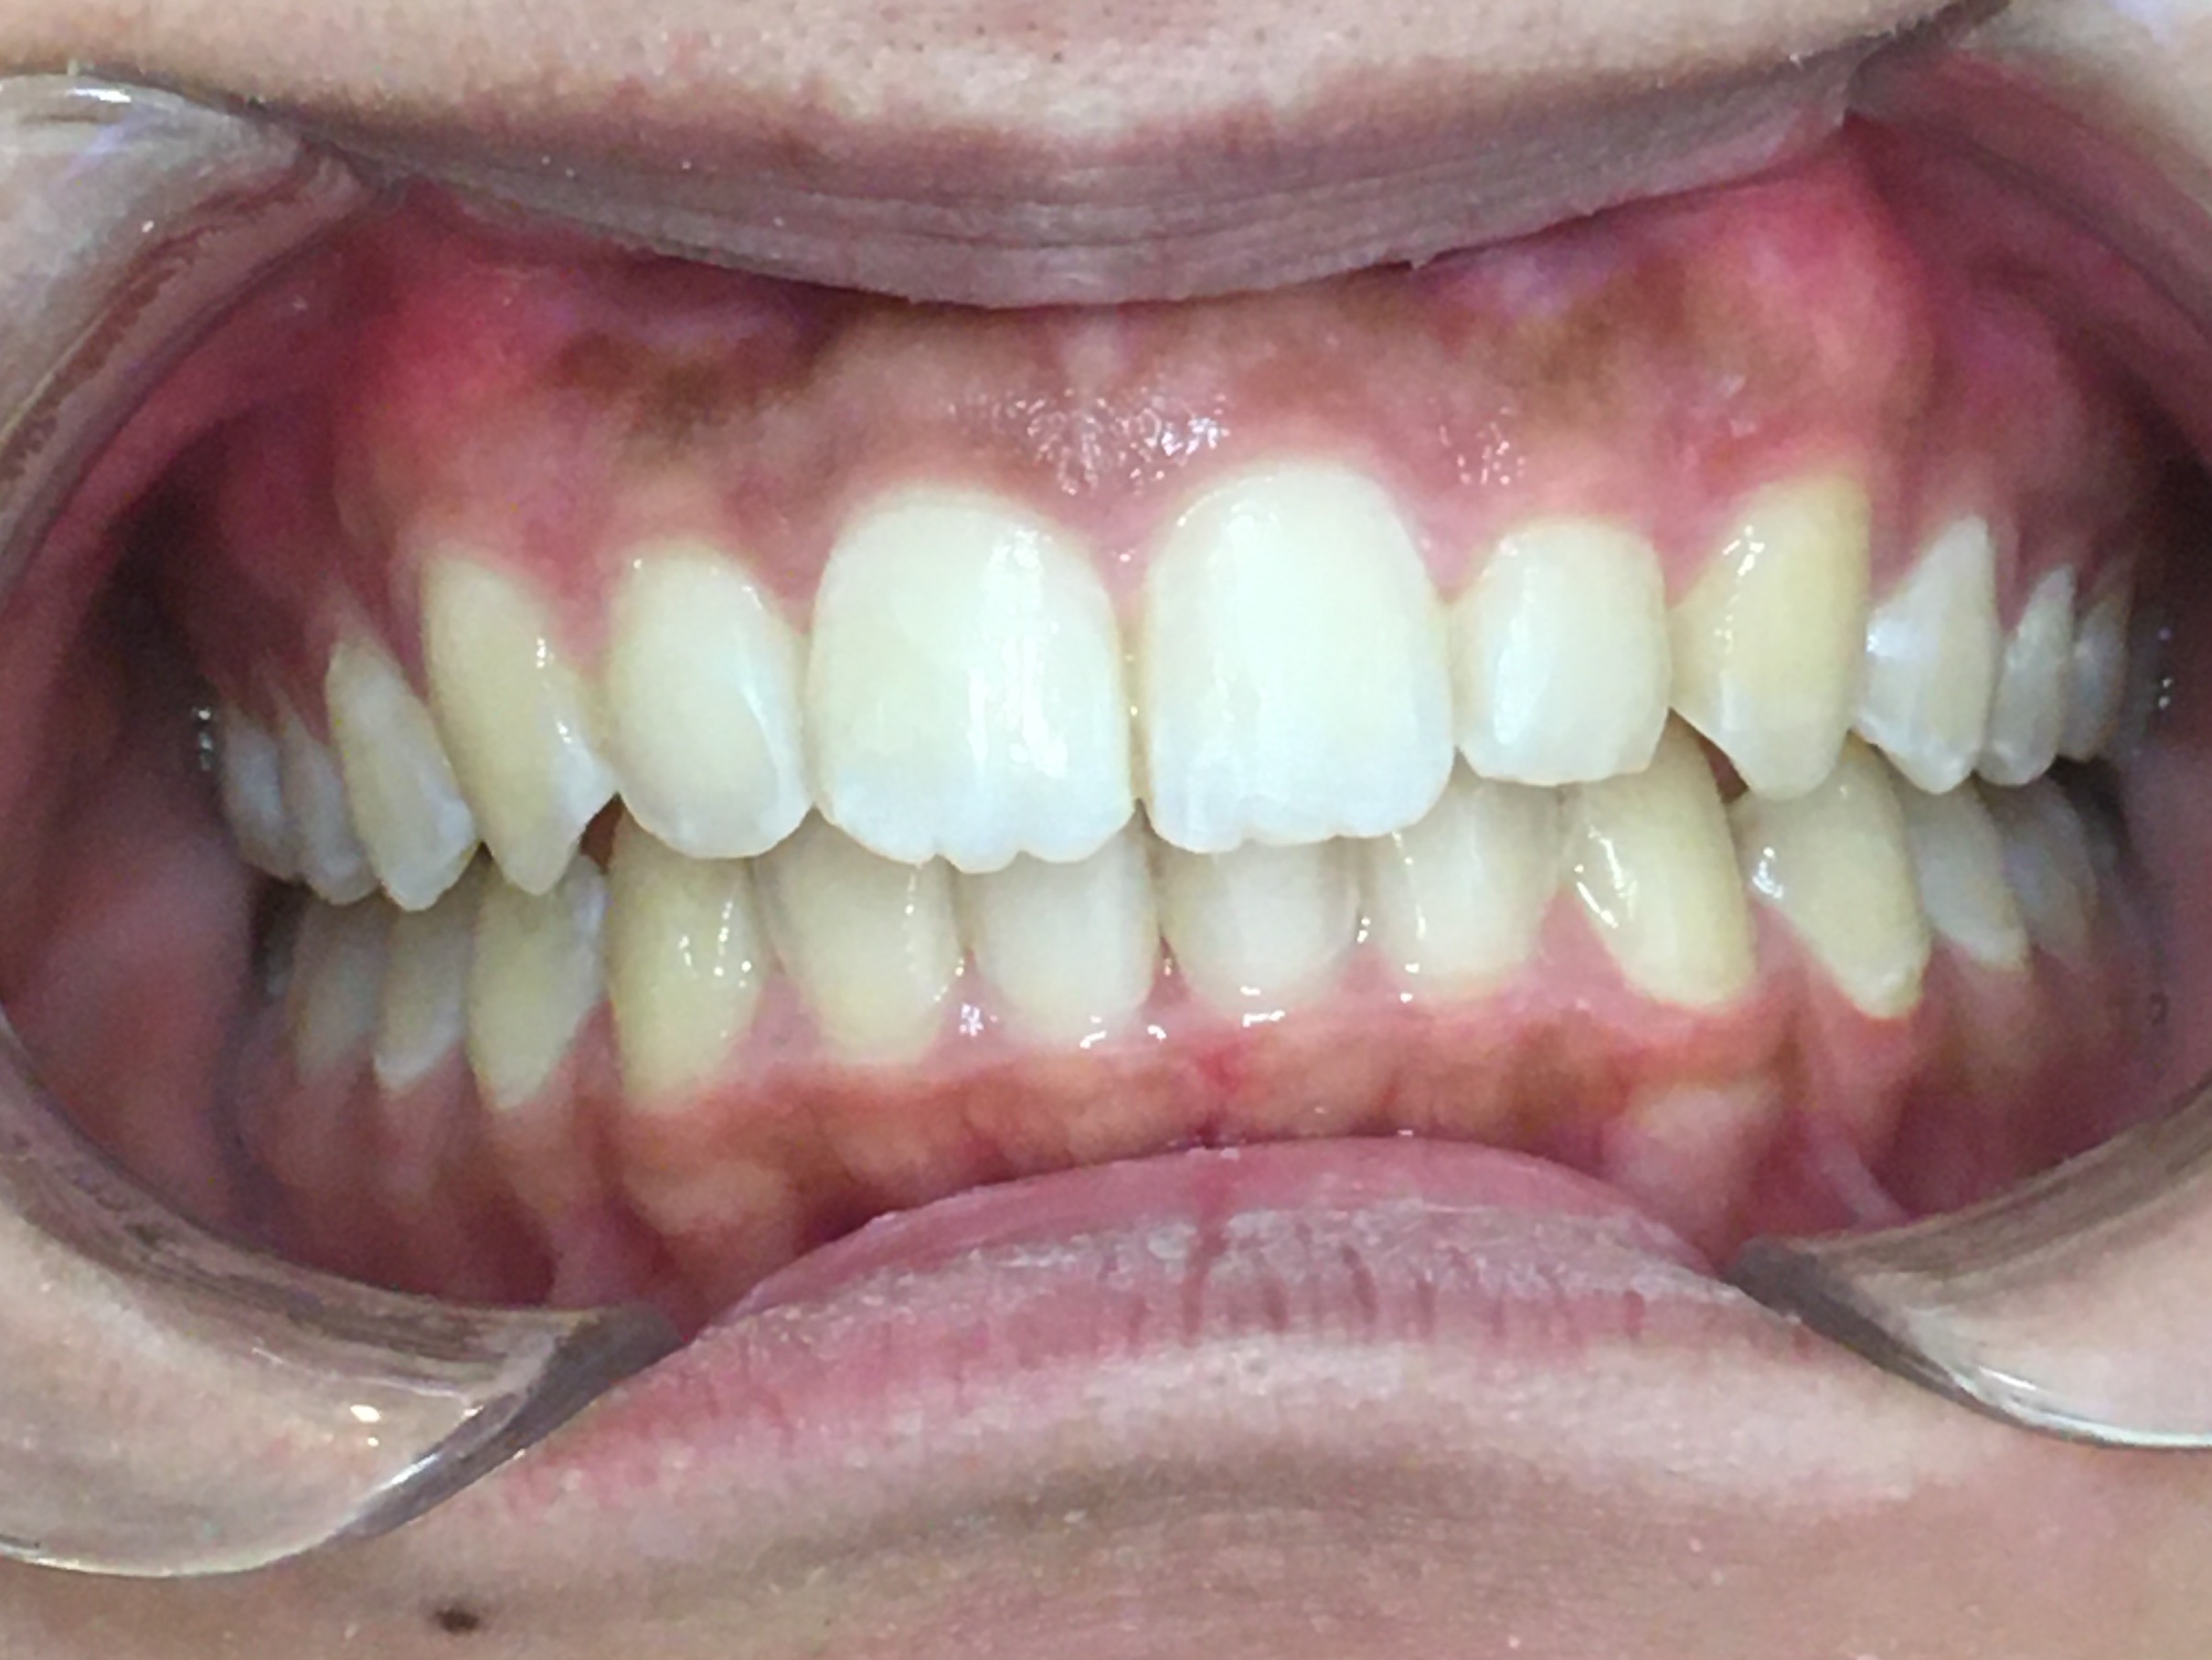

歯がまっすぐきれいに並び、噛み合わせも安定してしっかり噛めるようになりました。

患者様にも「口元が気にならなくなり嬉しい」と非常にご満足いただきました。

現在は歯並びの後戻りを予防するための「保定装置」をご使用いただき、経過を拝見しています。